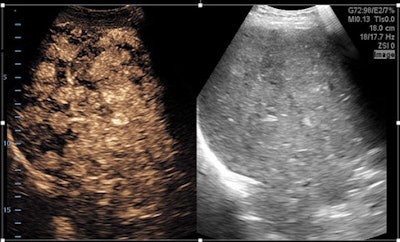

To compare traditional images with the enhanced SSCTRF images, the researchers collected contrast ultrasound loops from a Zonare ZS3 ultrasound system (Mindray) using two different transducers. The loops were processed with traditional methods, extracting single cubic-fundamental and single B-mode images.

The image data were also processed to extract up to six cubic-fundamental images and three harmonic images along with three B-mode images. The six cubic-fundamental images consisted of two images created by weighting and adding combinations of the pulse sequence, and four images that were then constructed through SSCTRF techniques to generate two steered-left and two steered-right images. The same technique was used to generate three standard harmonic and three B-mode images. The traditional images were compared with the SSCTRF images.

Image loops generated using SSCTRF techniques showed improved contrast resolution, better signal-to-noise ratios, and sharper border delineation, and preserved tissue perfusion kinetics without destroying additional microbubbles, providing enhanced visualization and higher diagnostic confidence, McLaughlin said.